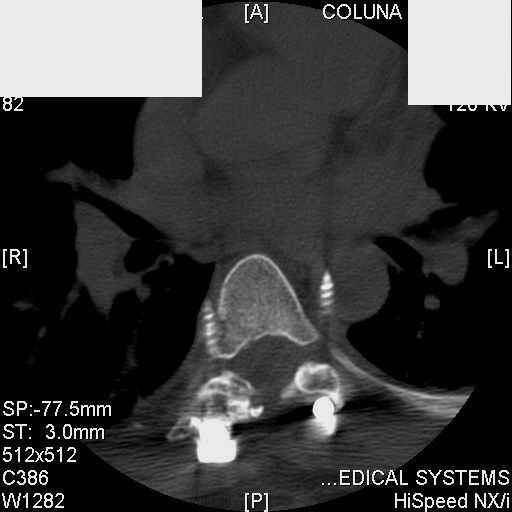

Interesting case. Findings on CT: all four pedicle screws have been placed improperly inthat they miss the vertebral bodies. In addition, the screws on the left side are impingingon the decending thoracic aorta. What I do NOT know is the nature of the original injury, orwhether or not that injury has resolved. I would recommend removal of the hardware. I don'tthink it's a good idea to leave those screws where they are. If the original fracture ishealed, nothing else needs to be done.

dear Mark, all the details are not yet available but the patient is coming to see us foradvice. We probably will see him in the early new year. i thought that the 4th picture showedthe screw to enter the aorta? He is a victim of a motor vehicle crash and thoracic vertebralfracture which appears healed. He was posteriorly decompressed and this device inserted. asyou say there isno evidenece that any of the fixation enters the bodies via the pediclesistead they have passed thru and their end are no where near where they ought to be. If I amcorrect (I would prefer not to be) the aortic intima has been breached by the screw. When thetime comes to take the screw out I thought we should have control of the aorta.What do you think?

Mark Thank you. He is scheduled for a angio prior to transfer here. I keep going back to lookat that fourth image and although it is tough to believe the wall of the aorta seems toencompass the distal 1/2 of the screw. I have come to anticipate mal postion of screws thathave been inserted in hospitals that perhaps may not have the highest quality of equipment,including the human and radiological components. That having been said this case seems tosurpass the usual... one screw out of place or screwed into a disc etc. BTW I am notsuggesting that the screw was placed directly into the aorta but that moviment, pulse actionetc may have caused it to transgress the normal anatomical bounds without evident hemorrhage.

Tom: I think it's easy to be misled by CT scans. I'd bet a bottle of good Scotch whiskeythat the aorta is uninjured.

Подошли ангиограммы... Наслаждайтесь...